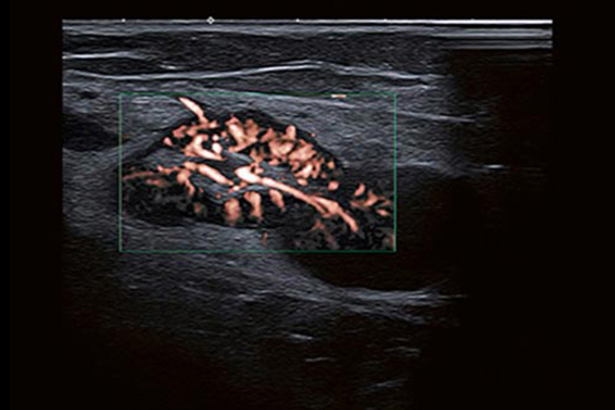

SMI帶來精細和清晰的彩色多普勒血流成像。SMI擴展了可見血流的范圍。低速微血流,SMI可以呈現(xiàn)。